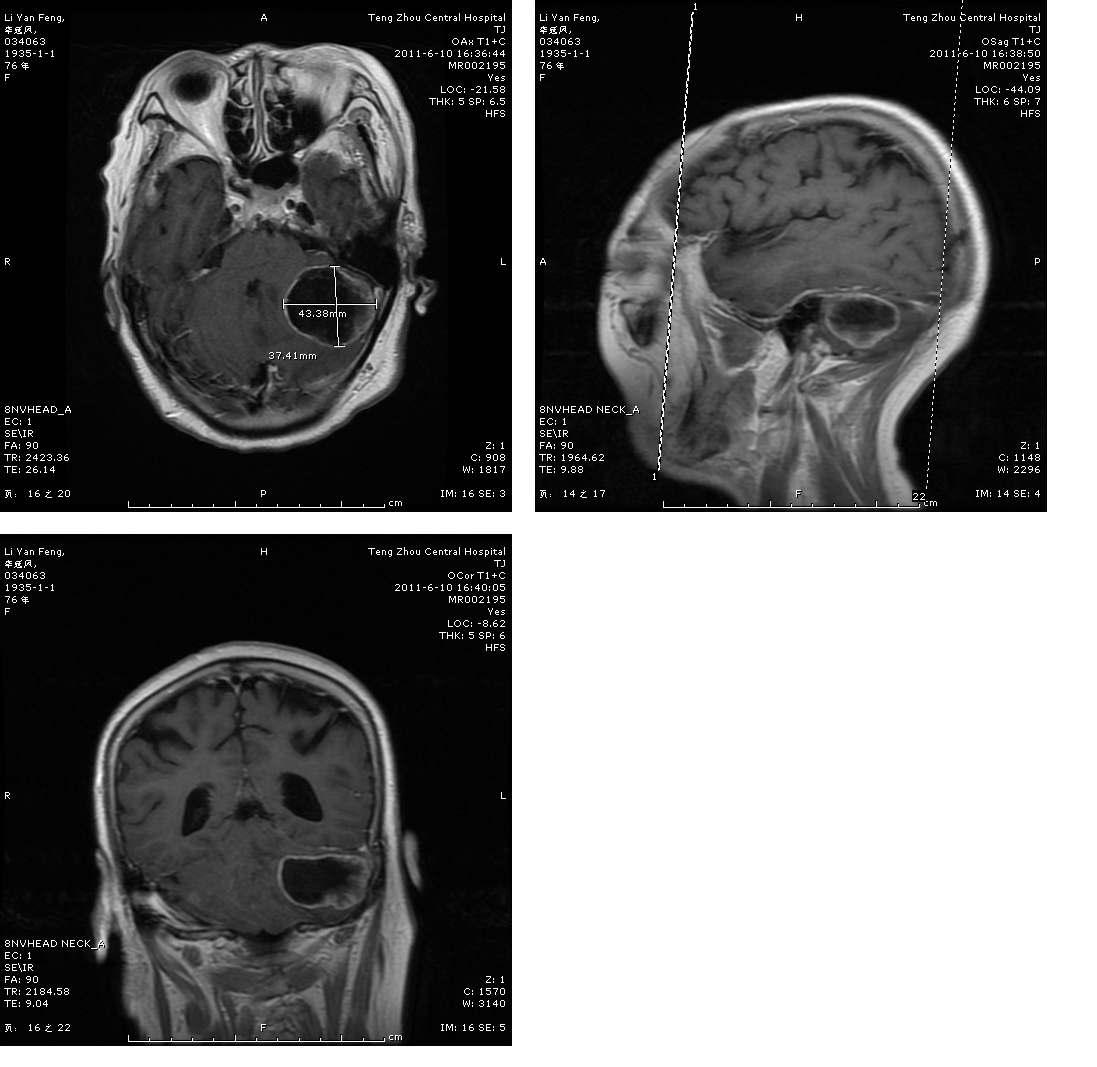

轉移瘤切除術前

轉移瘤切除術后